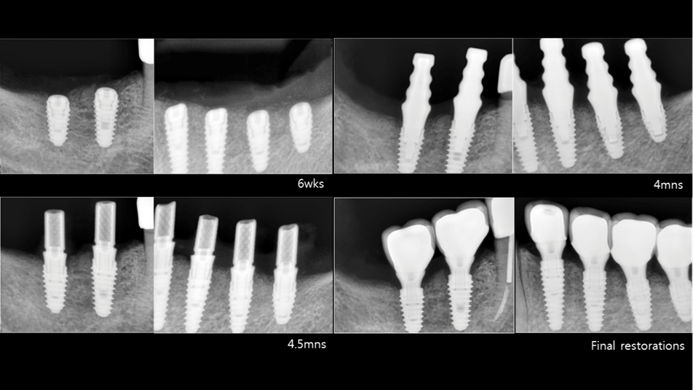

Clinical case: # 46 implant placement & GBR using i-Gen membrane for significant vertical resorption & mixed bone defect

- Courtesy of Dr. Iulian Filipov, Romania -

AnyRidge, mandibular posterior, i-Gen, resorption, bone defect, bone regeneration, space management, #46, GBR, Dr. Iulian Filipov